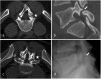

Low back pain (LBP) is the most common pain syndrome, and is an enormous burden and cost generator for society. Lumbar facet joints (FJ) constitute a common source of pain, accounting for 15-45% of LBP. Facet joint degenerative osteoarthritis is the most frequent form of facet joint pain. History and physical examination may suggest but not confirm facet joint syndrome. Although imaging (radiographs, MRI, CT, SPECT) for back pain syndrome is very commonly performed, there are no effective correlations between clinical symptoms and degenerative spinal changes. Diagnostic positive facet joint block can indicate facet joints as the source of chronic spinal pain. These patients may benefit from specific interventions to eliminate facet joint pain such as neurolysis, by radiofrequency or cryoablation. The purpose of this review is to describe the anatomy, epidemiology, clinical presentation, and radiologic findings of facet joint syndrome. Specific interventional facet joint management will also be described in detail. TEACHING POINTS: • Lumbar facet joints constitute a common source of pain accounting of 15-45%. • Facet arthrosis is the most frequent form of facet pathology. • There are no effective correlations between clinical symptoms, physical examination and degenerative spinal changes. • Diagnostic positive facet joint block can indicate facet joints as the source of pain. • After selection processing, patients may benefit from facet joint neurolysis, notably by radiofrequency or cryoablation.